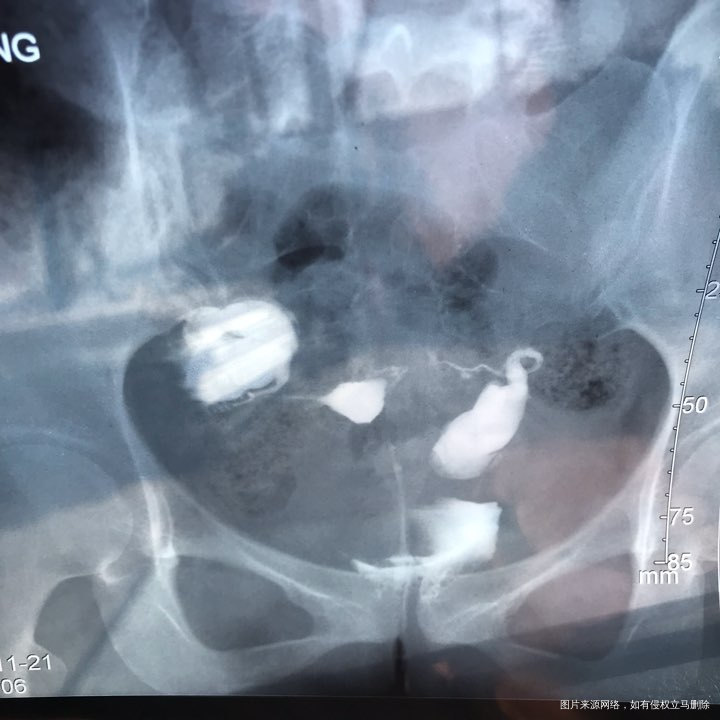

备孕时常1年,前期的检查都做了正常,帮忙看下我的输卵管造影片子吧??

您好,看着像是伞端堵塞了。

您好,考虑输卵管堵塞。建议遵医嘱。

您好,输卵管堵塞,建议切除输卵管做试管,保守保守治疗没有多大意义,觉着我的回复对您有帮助记着帮忙点击采纳,谢谢!